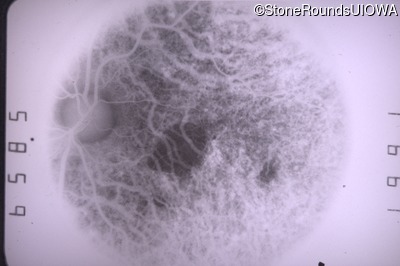

Fluorescein Angiography - Right - 20/25 sc

Exemplar